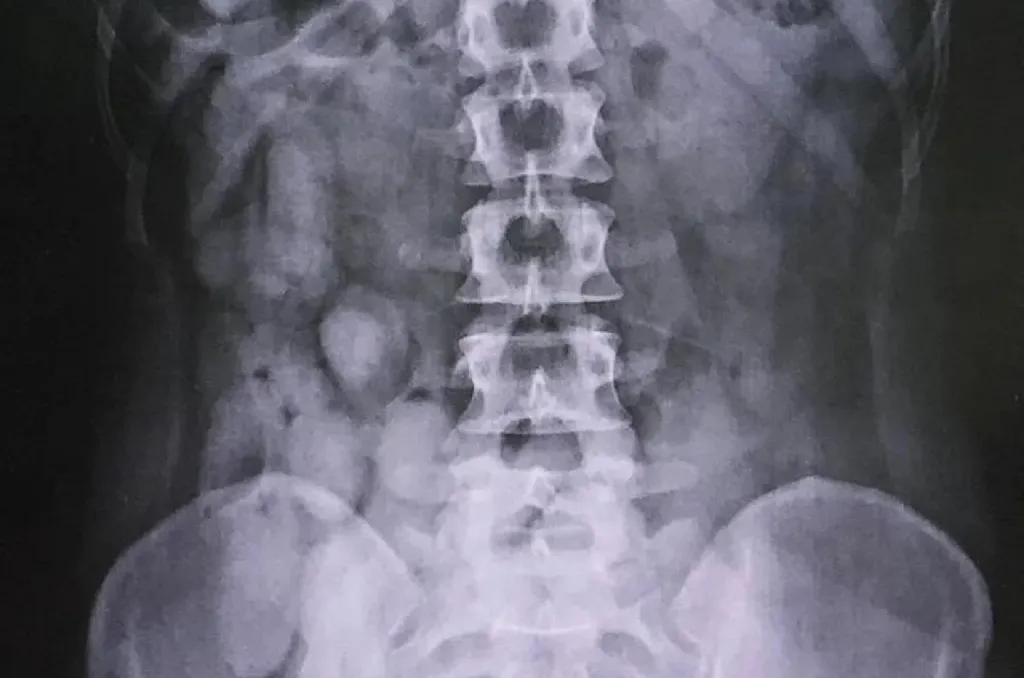

A kiérkező egyenruhások megmotozták őket, és átkutatták a ruházatukat, de nem találtak semmi gyanúsat a három kenyai nőnél. Ezt követően a kórházba szállították őket, ahol a röntgen már egészen mást mutatott.

Gyomrukban kapszulákat, vaginájukban pedig szintén kábítószert tartalmazó rudakat rejtegettek.

Összesen 2857 gramm, tehát közel három kiló tiltott anyag került elő mintegy 10 millió bath, vagyis több mint 100 millió forint értékben.